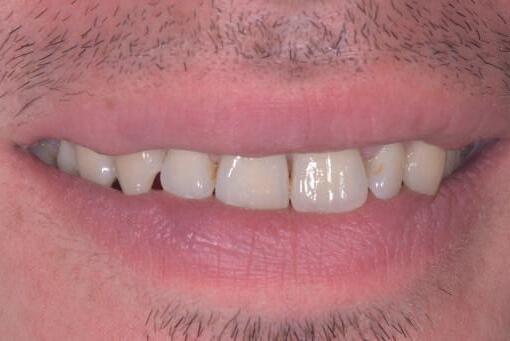

Si presenta alla nostra attenzione un paziente maschio, 35 anni, in apparente salute sistemica, fumatore, con la richiesta di controllare delle white spots, una leggera sensibilità e la richiesta di migliorare la luminosità del suo sorriso. Viene compilato e firmato il consenso informato. Il paziente viene motivato ad più efficace controllo del biofilm batterico e attraverso la condivisione dell’immagine clinica della topografia del biofilm batterico, (T.B.M.) scegliamo lo scovolino in gomma GUM Soft-picks (Sunstar) e lo sollecitiamo all’uso efficace degli spazi sovracrestali e allo spazzolamento in maniera delicata ma efficace della lingua. Sottoponiamo il paziente alla terapia parodontale non chirurgica con ablatore Comby touch (MECTRON) in modalità soft-mode per contenere la sua sensibilità. Valutiamo la sensibilità e modifichiamo i suoi stili di vita di igiene orale, di igiene alimentare e chiediamo di smettere di fumare. Il paziente riferisce di non essere disposto a rinunciare al fumo e chiediamo di ridurre il rischio di patologie e di discromie

da tabagismo passando all’uso dei dispositivi a tabacco riscaldato. Successivamente rileviamo il colore, con spettrofotometro, e con scala-colori Vita e documentiamo fotograficamente la condizione clinica presente.

Il colore rilevato è A2. Sottoponiamo il paziente ad uno sbiancamento pro-